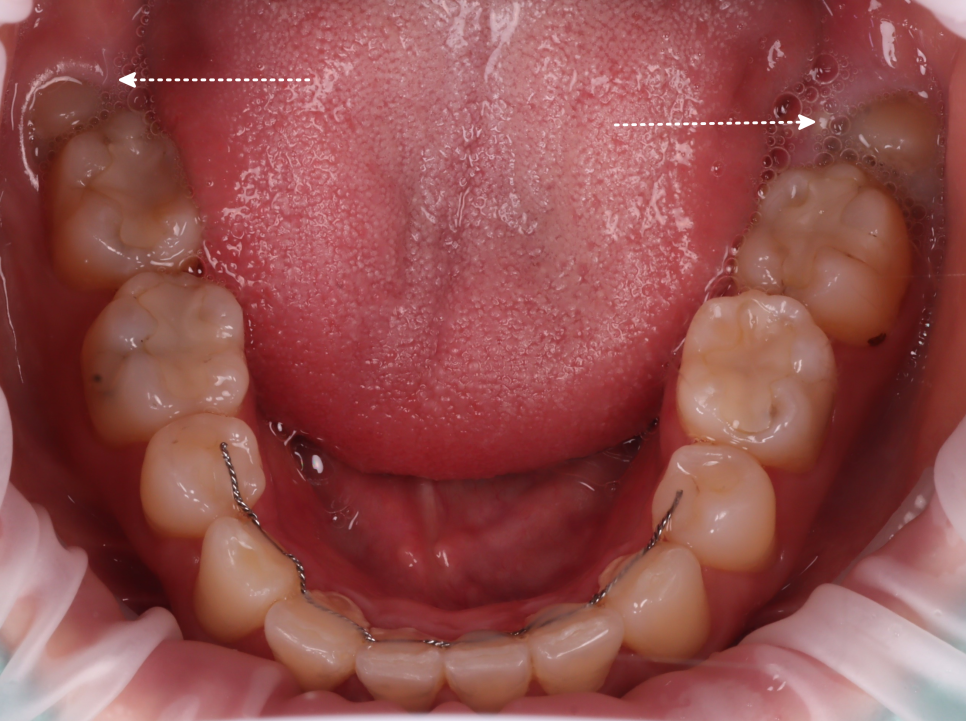

잇몸 속에 묻혀 있는 형태는 육안으로 확인하기가 힘들어서 엑스레이를 통해 정확한 상태를 확인해 봤는데요.

촬영일 : 251121

위쪽은 똑바로 나있었지만 아래 사랑니가 모두 매복 되었고 뿌리가 두 갈래로 갈라져 있었으며, 끝이 많이 휘어 있는 형태였어요.

또, 뿌리 끝과 하치조신경관의 거리가 매우 가까웠는데요.

이런 경우, 발치하다가 하치조신경관이 손상되는 경우도 있어서 매우 조심해야 됩니다.